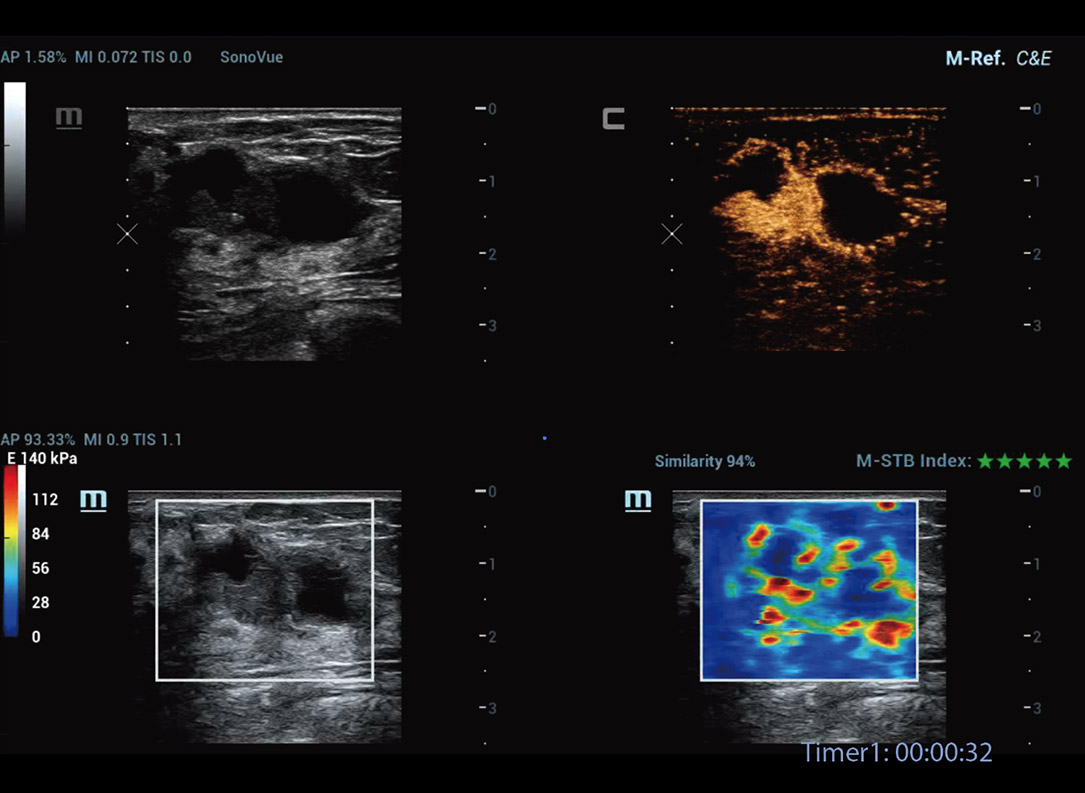

M-Reference E Compare

Strain e Shear wave juntos inspiram o futuro

M-Reference C&E

CEUS e Shear wave juntos desvendam o mundo do ultrassom multiparamûˋtrico

Ferramentas de anûÀlise multiparamûˋtrica M-Reference

M-Ref. C&E

M-Ref. C&E ã Tumor maligno de mama

M-Ref. C&E permitea exibi??o do contraste e da STE em um û¤nico plano para avalia??o comparativa de perfus?o e elasticidade.

M-Ref. E Compare

M-Ref. E Compare ã Tumor maligno de mama

M-Ref. E Compare oferece suporte û exibi??o tanto da elastografia por deforma??o em tempo real quanto da STE em um û¤nico plano para avalia??o da rigidez do tecido.